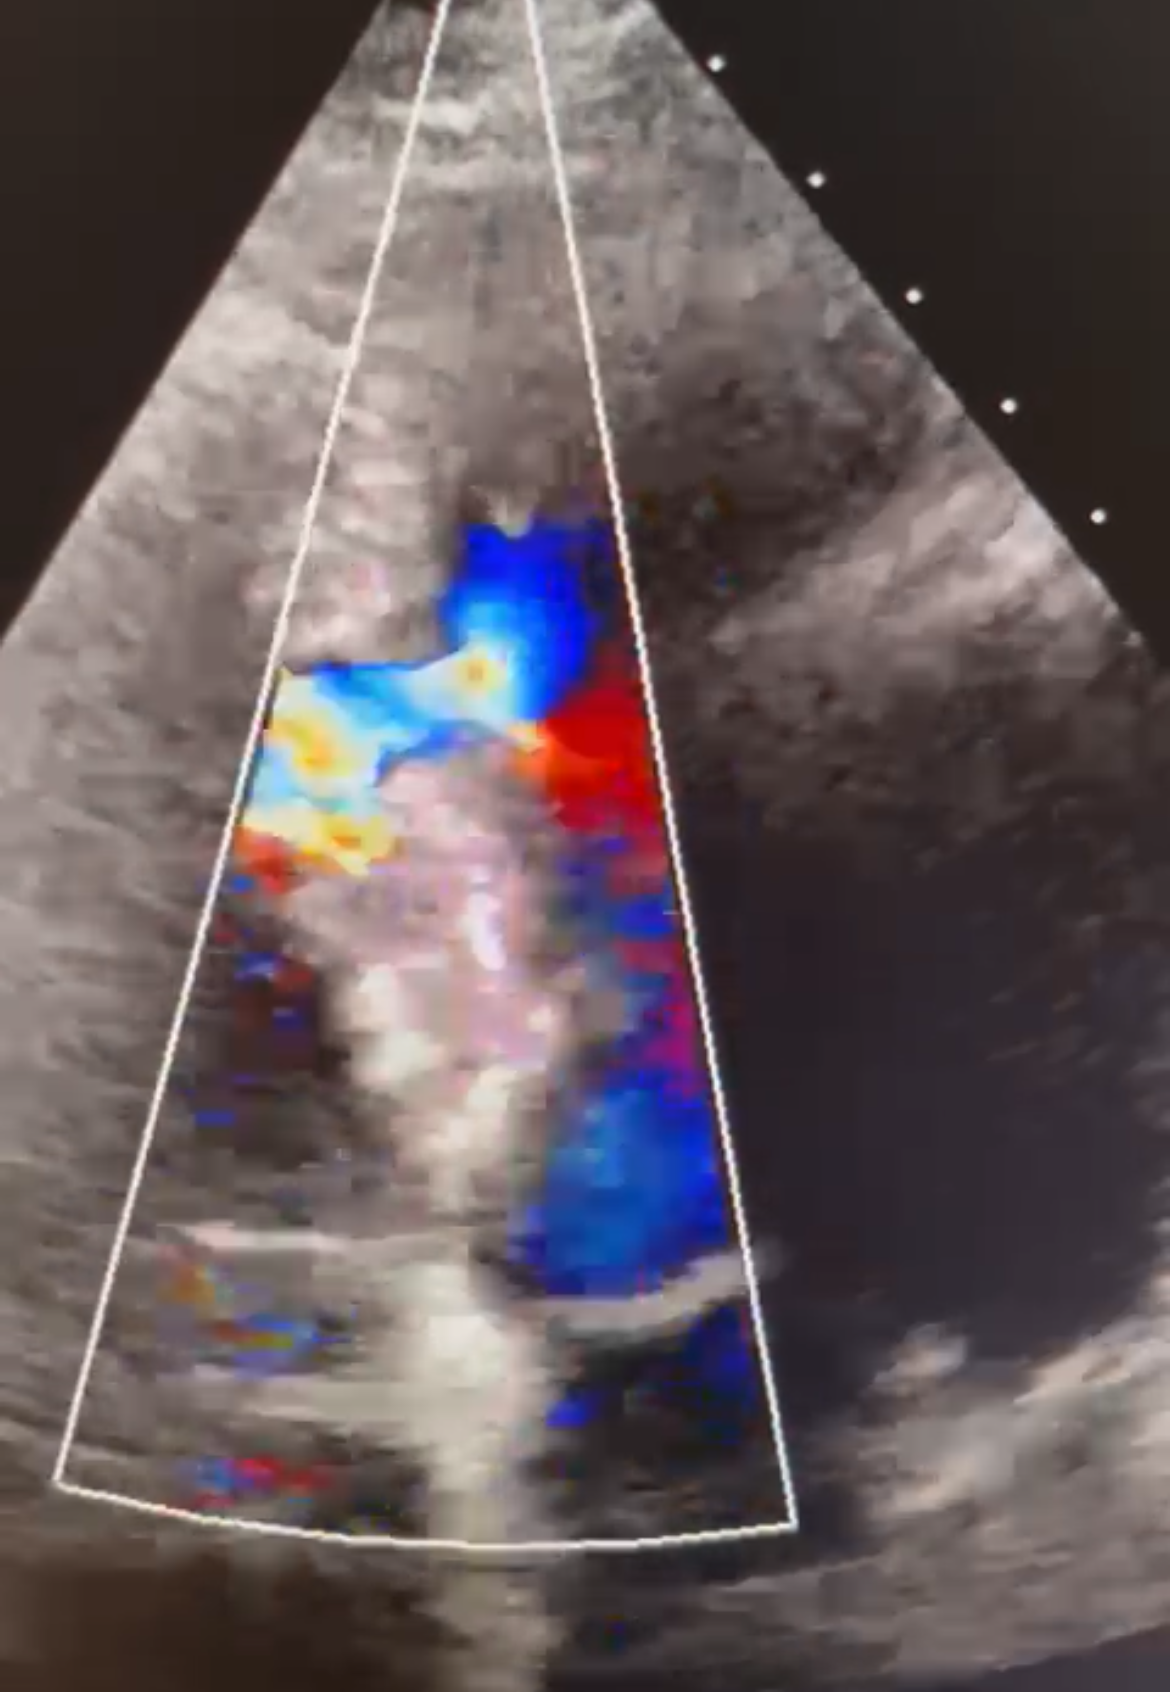

Soul2Heart is opgericht met het doel om de beste echocardiografische zorg te bieden. Ik streef ernaar om de gezondheid en het welzijn van patiënten te verbeteren door middel van nauwkeurige en betrouwbare hartonderzoeken. Met de huidige geavanceerde technologieën en een patiëntgerichte benadering zorgt Soul2Heart voor een uitstekende diagnostische ervaring.

Ik ben gecertificeerd cardiaal echografist met uitgebreide training en ervaring in echocardiografie. Ik werk graag met een breed scala aan patiënten met diverse hartgerelateerde aandoeningen. Mijn nauwkeurigheid, geduld, empathie en kunnen communiceren in meerdere talen, Engels – Frans – Spaans – basis Arabisch, maken mij een gewaardeerde professional in dit vakgebied.